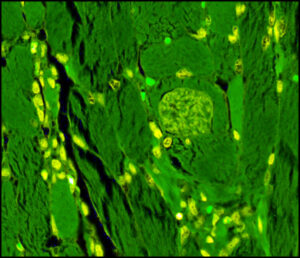

What is Sarcocystis? Sarcocystis is a genus of single-celled parasites with a complex lifecycle involving […]